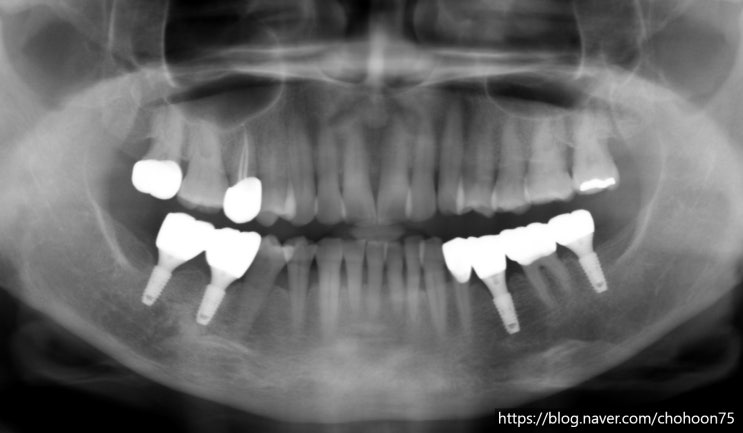

안녕하세요. 조훈 치과입니다. 오늘은 앞서 2021년 6월 조훈 치과 블로그에 포스팅하였던 케이스로 최근의 ...